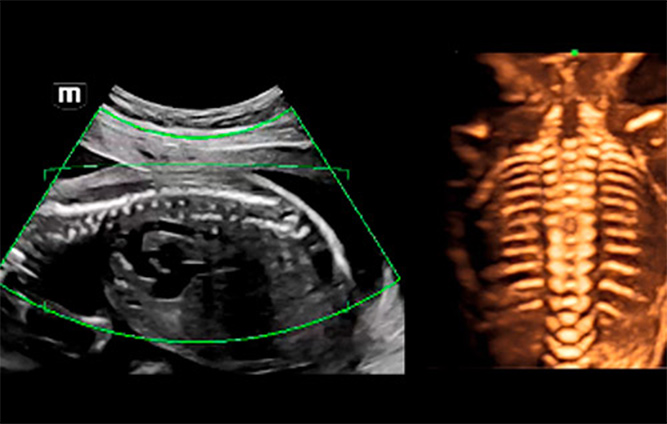

Fetal omurgan?n 3B/4B ultrason g?rÞntÞleri